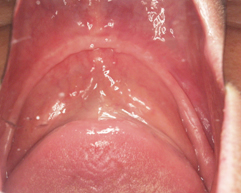

治療前

院長の吉本の診断は以下でした

入れ歯を何年も使っていて、よく噛んでいたために骨の厚みがうすく細くなっています。これでは、入れ歯は安定しません。

本来、骨の中にうまっている神経が骨が溶けることによって歯茎の上から触れることができます。

それが、入れ歯を入れるだけで痛い理由です。